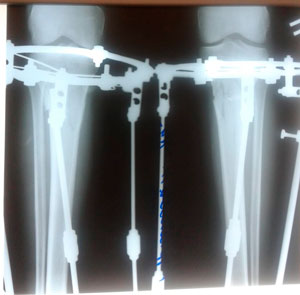

Дата снятия аппаратов- 26.07.2019г.

Срок сращения -87 дней.